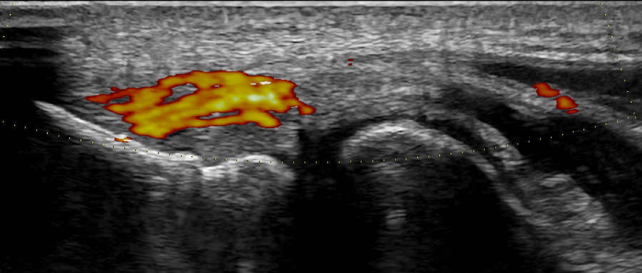

▎一、手肘外側疼痛 ─ 網球肘

長期使用電腦、過度出力或運動後常見之網球肘(肘外側伸肌肌腱病變),臨床上可從位置診斷;但搭配超音波儀器檢測,更可精細診斷肌腱腫脹或發炎,嚴重者可能合併肌腱局部撕裂、橈側副韌帶損傷,或有壓迫周邊細微的皮神經等,此時可考慮搭配局部注射治療。

圖說:超音波影像下,可見手肘外側伸腕肌群的共同肌腱血流增加,意即組織發炎。